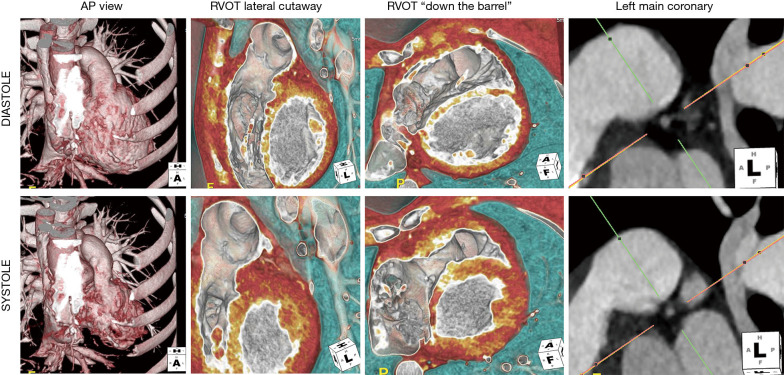

随着患有先天性心脏病(ACHD)的成人人数的增加,对非侵入性监测方法的需求也在扩大,以指导管理和干预。多模式成像方法将超声心动图、计算机断层扫描(CT)、磁共振成像(MRI)和其他模式的互补见解分层,纳入临床医生对患者生理学的看法。仅仅应用获得性成人心脏病的策略是不充分的,并且可能具有误导性。随着数据在这个小而不断增长的人群中积累,ACHD领域的研究人员已经发现了特定人群的成像生物标志物,可以识别恶化和关键时间点,干预可以降低发病率和死亡率。此外,由于ACHD患者的生理变化多样,而且与成人获得性心脏病患者相比,ACHD患者的数量较少,因此多中心登记将是推进研究的关键。将定义良好的成像变量整合到这些数据库中可以帮助识别重要的生物标志物。计算流体动力学(CFD)和人工智能(AI)等新兴技术也有望增强成像能力和临床工作流程,但需要仔细调整,因为这些技术的培训数据中并没有有意义的代表ACHD患者。最终,多模态成像方法对于优化ACHD患者的护理至关重要,可以在临床恶化发生之前进行个性化医疗干预。

As the population of adults with congenital heart disease (ACHD) grows, there also grows an expanded need for non-invasive surveillance methods to guide management and intervention. A multimodal imaging approach layers complementary insights from echocardiography, computed tomography (CT), magnetic resonance imaging (MRI), and other modalities into a clinician's view of patient physiology. Merely applying strategies from acquired adult cardiac disease would be inadequate and potentially misleading. As data amasses in this small but growing population, investigators in the field of ACHD have discovered population-specific imaging biomarkers that identify deterioration and pivotal time points where intervention may reduce morbidity and mortality. Moreover, due to the variety of physiologies and the modest number of ACHD patients relative to that of adults with acquired heart disease, multicenter registries will be key in advancing research. The integration of well-defined imaging variables into these databases can help identify important biomarkers. Emerging technologies like computational fluid dynamics (CFD) and artificial intelligence (AI) are also primed to enhance imaging capabilities and clinical workflows, though require careful adaption as ACHD patients are not meaningfully represented in the training data for these technologies. Ultimately, a multimodal imaging approach is essential for optimizing care for ACHD patients, enabling personalized medicine where interventions can be performed before clinical deterioration occurs.